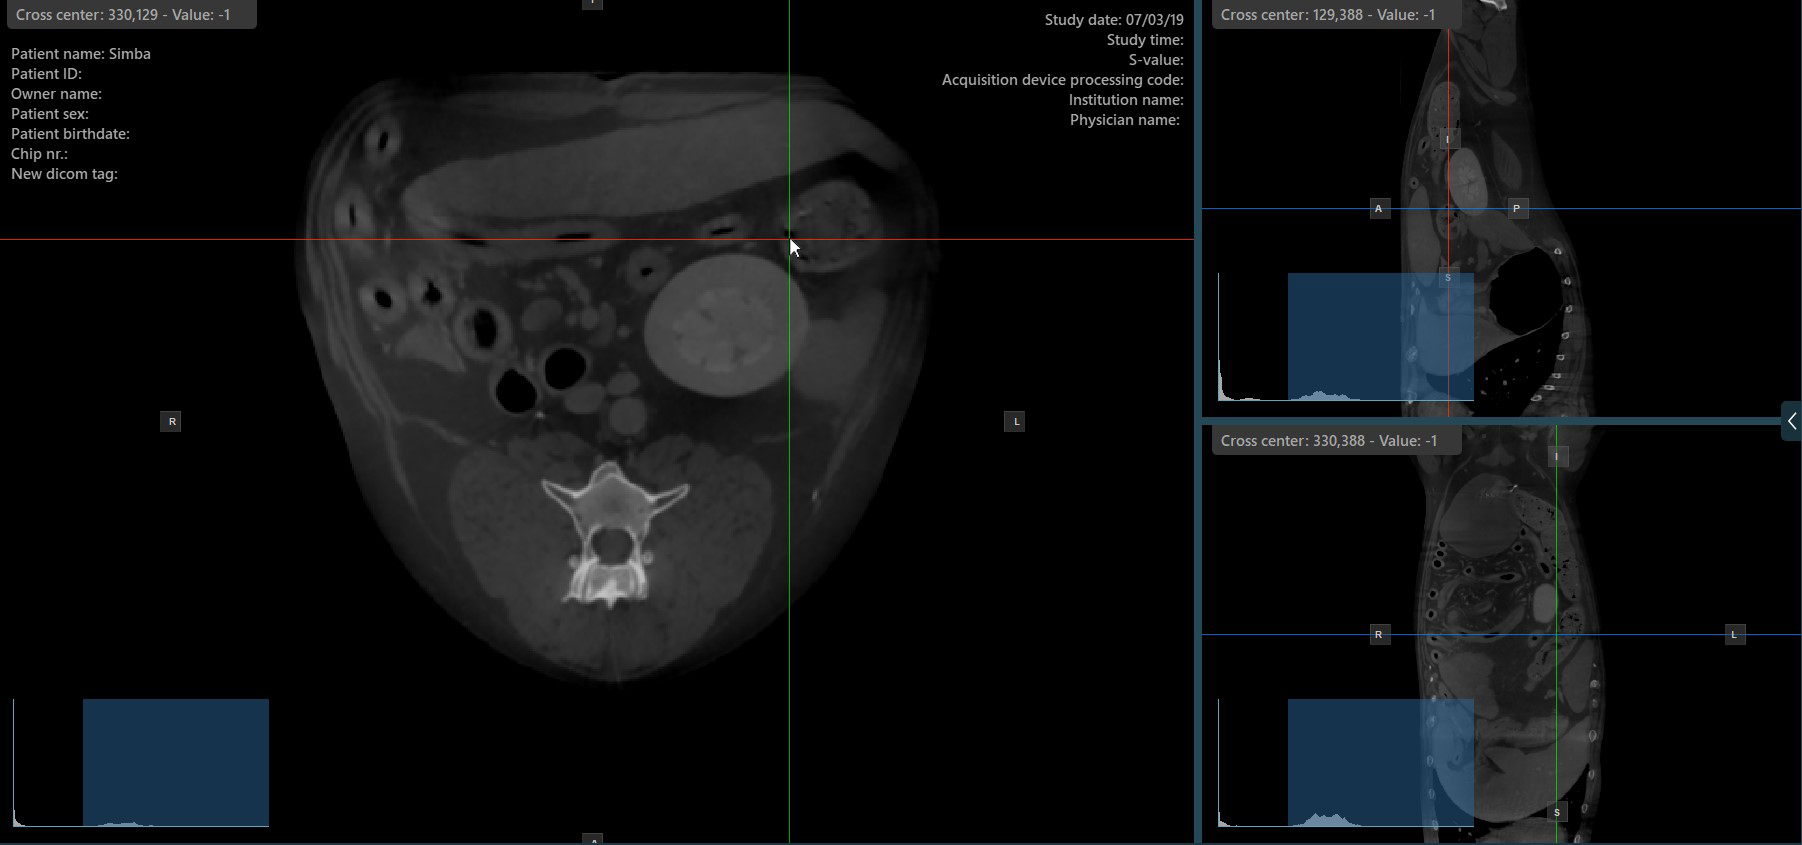

Change Slicers Cross Center Position¶

Altering the position of the cross center of slicers will change the position of the corresponding two image planes. The cross center of the slicers can be selected by using the Select Item (Default) tool, assigned to the right mouse

button by default.

Once selected, drag the cross center of the specific slicers to the desired direction to move its position. The corresponding image planes’ orientation changes accordingly.